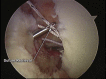

Posterior shoulder dislocation is an unusual injury often associated with electrical shock or seizure. As with anterior instability, patients frequently present with an impaction injury to the anterior aspect of the humeral head known as a "reverse Hill-Sachs lesion." The treatment of this bony defect is controversial, and multiple surgical procedures to fill the defect in an effort to decrease recurrence have been described. Most of the reports have focused on an open approach using variations of lesser tuberosity and subscapularis transfers, bone allograft, and even arthroplasty to assist with persistent instability. We advocate an arthroscopic technique that involves a suture anchor-based distal tenodesis of the subscapularis tendon or a reverse remplissage procedure.